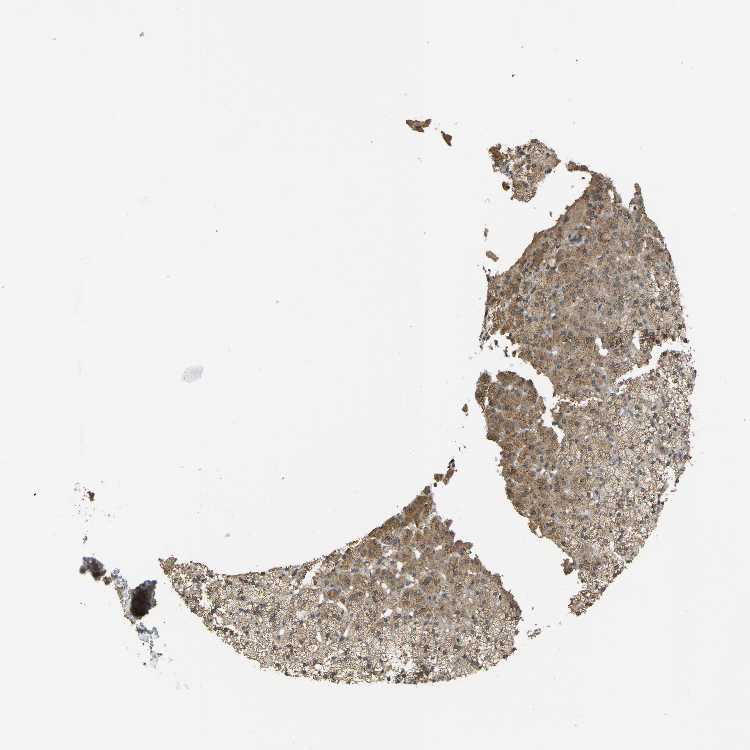

ADRENAL GLAND - Antibody stainingi

Antibody staining in the annotated cell types in the current human tissue is reported as not detected, low, medium, or high, based on conventional immunohistochemistry profiling in selected tissues. This score is based on the combination of the staining intensity and fraction of stained cells.

Each image is clickable and will lead to virtual microscopy that enables deeper exploration of all samples and also displays staining intensity scores, fraction scores and subcellular localization as well as patient and tissue information for each sample.

Antibody HPA018476Antibody CAB017618

Glandular cells MediumMedium